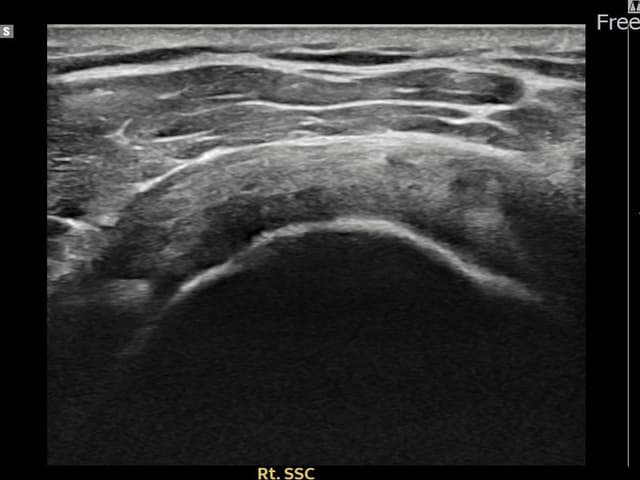

[촬영시기:22.09.19~22.12.09]

[어깨인대 축소봉합술] 우측 어깨 통증이 수개월간 지속되어 내원하셨습니다.